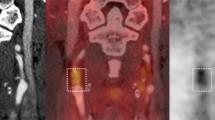

Assessment of vascular wall inflammation and atherosclerotic plaque FDG uptake activity was initiated by qualitative and visual scaling methods3,35 and changed over time to semi-quantitative and quantitative methods.14-17 In the recent years, most studies prefer to use semi-quantitative and quantitative measurements to evaluate FDG uptake activity of the vessel walls and atherosclerosis.4,39-41 To measure the vessel wall FDG uptake in a PET/CT image, regions of interest are placed around the outer boundaries of vessel walls in trans-axial views of PET/CT scan (either with or without contrast) (Figure 1A). Table 1 has summarized some semi-quantitative measurement indices that have been used by investigators. After measuring these semi-quantitative indices, some groups have described their own strategy for improving evaluation of FDG uptake activity in the plaques and inflammatory lesions within vessel walls and for comparing the disease activity between and within subjects precisely. These additional measurement strategies include index vessel selection and most diseased segment and active segment analysis,42 atherosclerosis burden and global inflammatory burden,43 global metabolic activity,44 and coverage extension and skipping the slices.45

Trans-axial views are commonly used to evaluate FDG uptake in the vessel wall. A circular region of interest is placed around the outer boundaries of the vessel (descending aorta) to measure FDG uptake in the vessel wall (A). Then, these numbers should be normalized to background activity which is measured from blood pool by drawing a region of interest inside the vessel (superior vena cava) lumen where there is minimal wall FDG uptake activity (B)